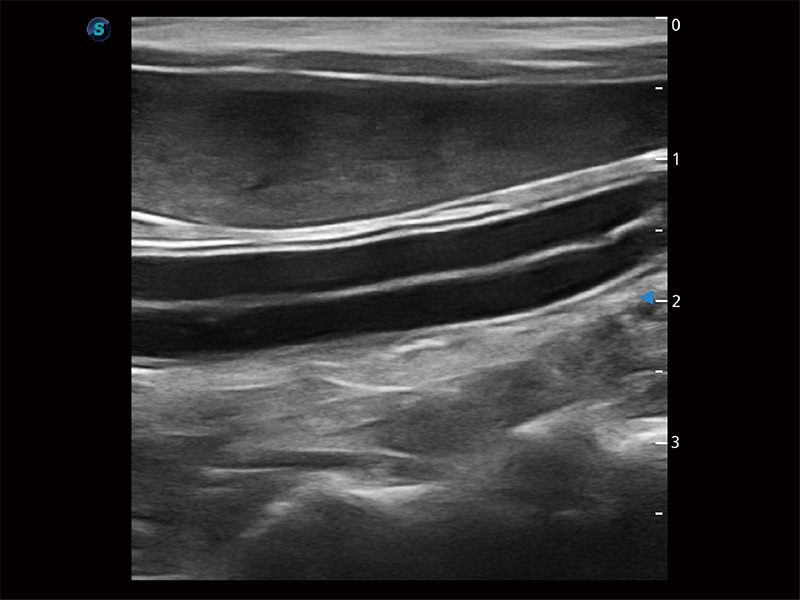

(犬)肠道